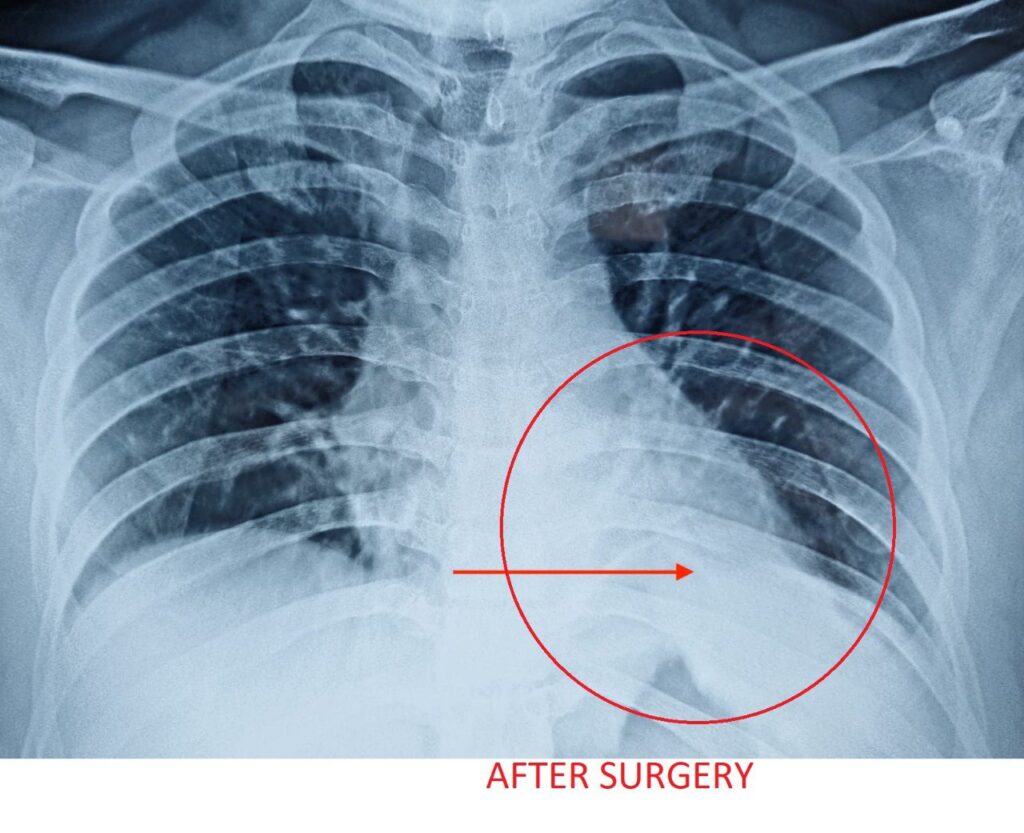

ओटीपोटावर फक्त ४ लहान कट होते आणि शस्त्रक्रियेनंतर रामसिंगच्या श्वासोच्छवासात त्वरित सुधारणा झाली शस्त्रक्रियेनंतर केलेल्या छातीच्या एक्स-रेमध्ये डायाफ्राम सामान्य स्थितीत दिसून आला. शस्त्रक्रियेनंतर रामसिंगला ४८ तासांत त्यांना डिस्चार्ज देण्यात आला.”